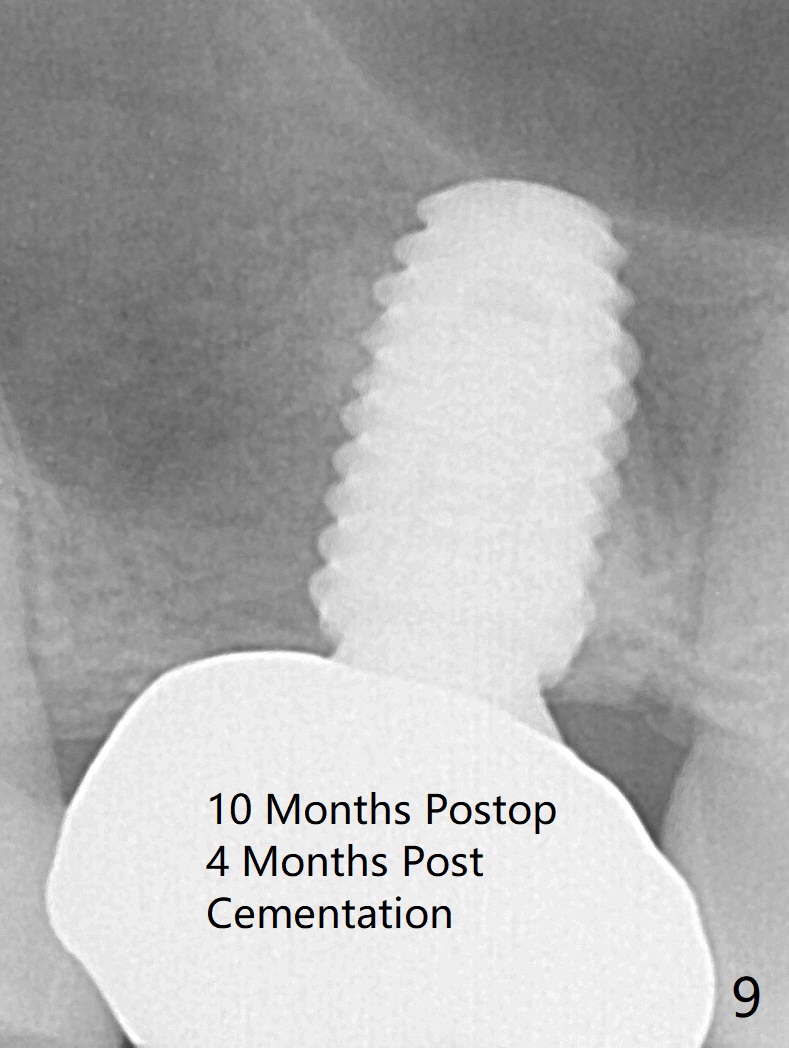

When the residual roots of the tooth #3 are removed, there is a gingival band over the septum (Fig.1 S). Osteotomy (Fig.2 yellow circle) would tear it off. To save the soft tissue, the buccal attachment is severed (Fig.3 black line), the flap is rotated palatal (Fig.3 curved arrow) and sutured in place (Fig.5 S). After sinus floor breakdown (use of sinus drill for 16 mm) and use of membrane lifter/water, two pieces of PRF membrane are inserted. The membrane is so slippery that it is easy to enter the sinus for further sinus membrane lift and later allograft placement (Fig.4 *). A 4.5x10 mm dummy implant is placed with high torque after 4x7.3 mm drill with 3 mm stopper so that 4.5x7.3 mm drill with 1 mm stopper is used before placement of a 5x8.5 mm final implant with ~ 35 Ncm (Fig.5-7). The patient reports anterior sinus wall tenderness with right nasal discharge a few days postop. The provisional has mobility without tenderness 1 week postop. It appears that the sinus membrane has been involved, which is quickly repaired probably by PRF. There is no pain when a 5.2x4(2) mm cemented abutment is torqued at 30-35 Ncm before impression (Fig.8). The surrounding soft tissue is healthy. When the permanent crown is delivered, the patient feels light pain when she bites hard. The discomfort persists 4 months post cementation (Fig.9). The crown/abutment is replaced with a healing abutment (Fig.10). There is no bone loss 4 months post healing abutment placement (14 months post implant placement, Fig.11). Upper Molar Immediate Implant, Prevent Molar Periimplantitis (Protocols, Table), Trajectory II, 31 Flap Not Transferred Xin Wei, DDS, PhD, MS 1st edition 07/26/2019, last revision 10/05/2020